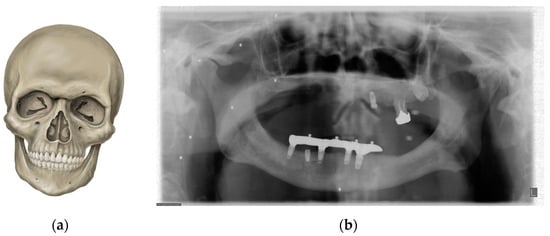

2. PAN Acquisition Principles

7. Metal and Motion Artefacts